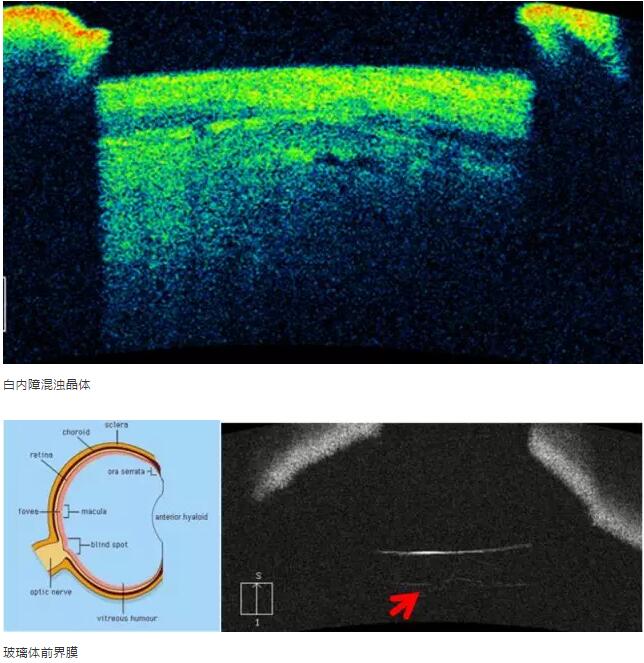

白内障篇

1:白内障混浊晶体观察

2:人工晶体位置观察